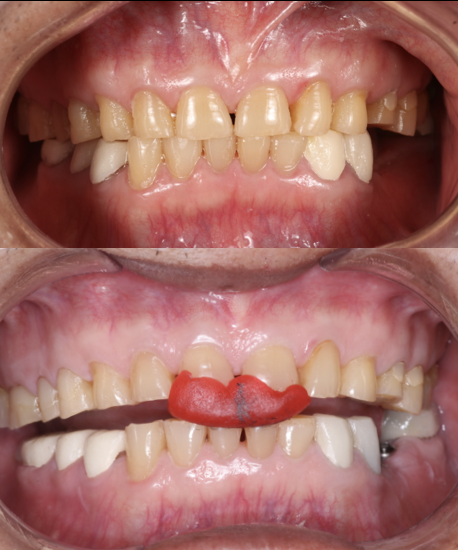

Before

After

Smile Makeover

This case involved an occlusal issue with Class III incisor malocclusion. The patient was treated with a comprehensive smile makeover, including crowns on #11 and #21, e-max veneers on adjacent teeth, and Beyond Plasma Whitening on the lower arch. The result is a beautifully balanced, brighter smile — both functional and aesthetic, proudly completed at Moral Dental Clinic.